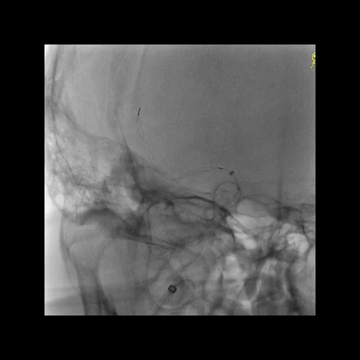

抽拉结合取栓后造影:颈内动脉远端和M1多发充盈缺损;更换6F中间管,且6F长鞘上高到C1远端。

微导丝微导管超选到M1下干。

微导管造影证实真腔,再次送入和释放支架。

抽拉结合取栓后造影示:闭塞完全再通,取出数块大血栓。